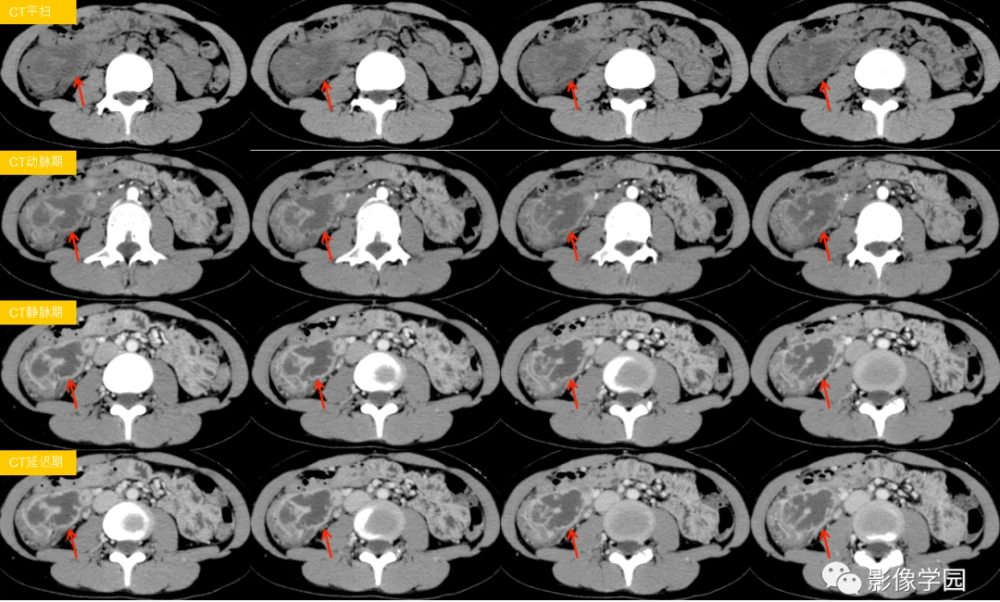

然后,医生还会让我去做一些检查,比如验血啊,做肠镜啊,看看肠子里有没有那些发炎的痕迹。有时候,还得做做CT或者MRI,看看肚子里的情况。这些检查听起来就让人紧张,但为了搞清楚到底是不是克罗恩病,也只能硬着头皮上了。